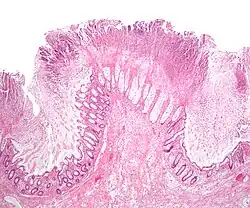

Before the advent of tests to detect C. difficile toxins, the diagnosis most often was made by colonoscopy or sigmoidoscopy. The appearance of "pseudomembranes" on the mucosa of the colon or rectum is highly suggestive, but not diagnostic of the condition.[46] The pseudomembranes are composed of an exudate made of inflammatory debris, white blood cells. Although colonoscopy and sigmoidoscopy are still employed, now stool testing for the presence of C. difficile toxins is frequently the first-line diagnostic approach. Usually, only two toxins are tested for—toxin A and toxin B—but the organism produces several others. This test is not 100% accurate, with a considerable false-negative rate even with repeat testing.[47]

Pseudomembranous colitis first was described as a complication of C. difficile infection in 1978,[112] when a toxin was isolated from people with pseudomembranous colitis and Koch's postulates were met.